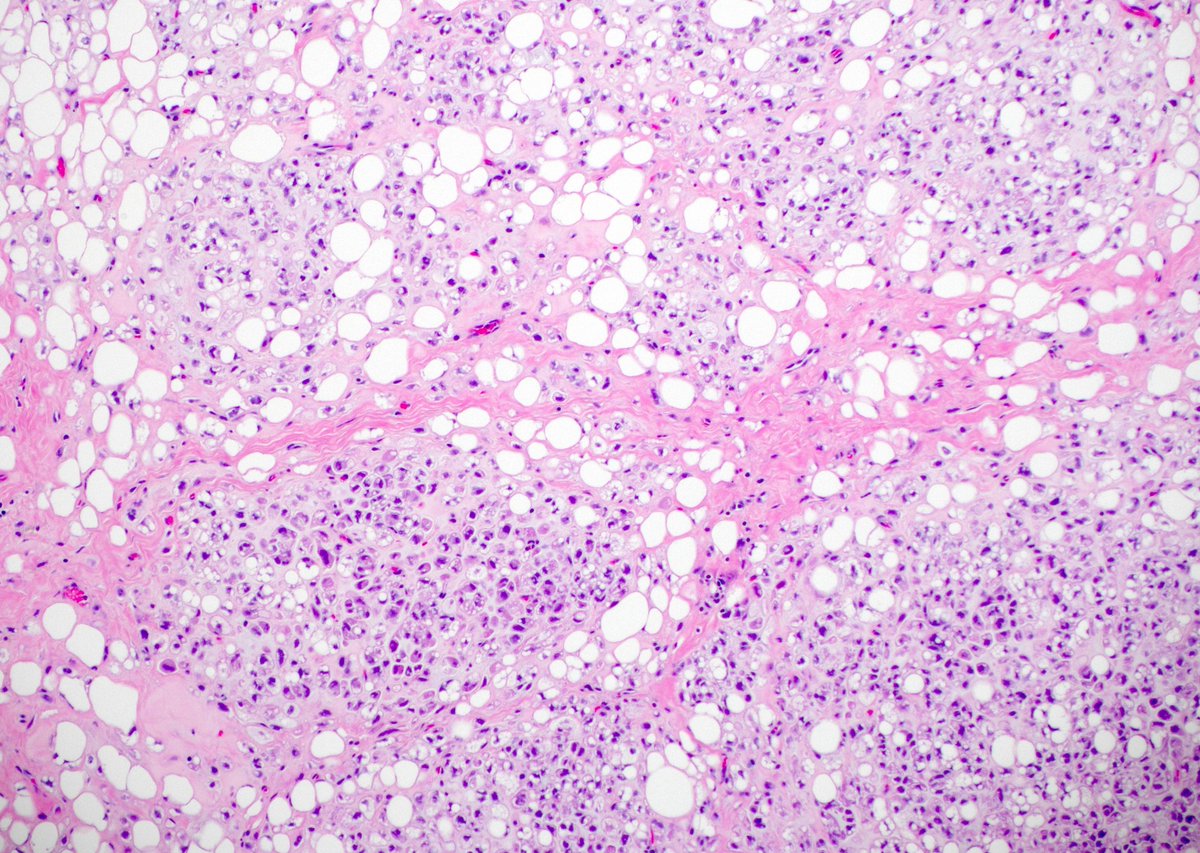

Silvija Gottesman MD Alejandro Gru (Ale) J Cutan Pathol Katy Veprauskas Maxwell Fung, MD Gregory A Hosler Henry YANG David Terrano Dermpath-L Dermpath_doc_trish Tristan Rutland MBBS FRCPA IFCAP Etan Marks, DO Maryam Aghighi, MD. DABP. Jerad Gardner, MD Cacey Peters, MD, FCAP, FASDP Pembe Oltulu, MD Walter Klein MD Andrea P Moy, MD Patrick Rush Jisun Cha MD FAAD Sara Shalin James A. Ramirez Joseph Susa, DO Rosalynn Nazarian MD 🅰🅼🆈🅷🅳🅴🅴🅺🅴🅽🅼🅳 Mariantonieta Tirado Vijay Shankar S Mike DeWall, D.O. Olaleke Folaranmi David Larson Luis Humberto Cruz C Kamran Mirza MD PhD - کامران مرزا Toño Navarro, M.D. 🔬🎗️ Nicole D. Riddle, MD, MSHI, FCAP (she/her) Haneen Salah Save the Date. Save the Date. Hot off the press. Next #dermpathJC to take place on 01/26/23 at 9pm EST, here on Twitter. Open access link at: jamanetwork.com/journals/jaman… #dermpath